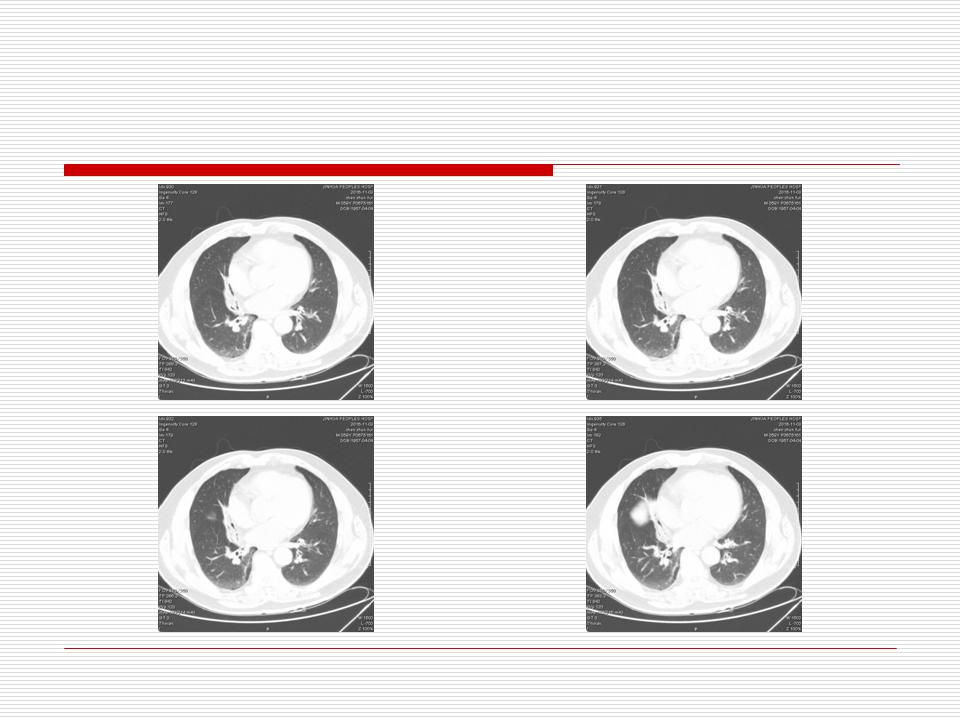

肺部阴影永恒且最重需要鉴别的是:到底是炎症还是肿瘤?但临床的病例中的影像表现难以界定或有些肿瘤特征,同时又有些炎症特点是非常常见的情况。作为临床医生我们怎么去总结分析,并找到之所以是炎症或之所以是肿瘤的细微差别或特点非常重要,也非常有用。2019.12.7浙江省2019年胸心外科学学术年会在宁波召开时,我的临床病例分析与经验总结<那些像肺癌的炎症与像炎症的肺癌>获得在大会交流的机会,以下为该PPT的内容,与你分享,希望对同道有益,有借鉴与启迪。若有探讨与进一不完善的建议,欢迎文末留言讨论: